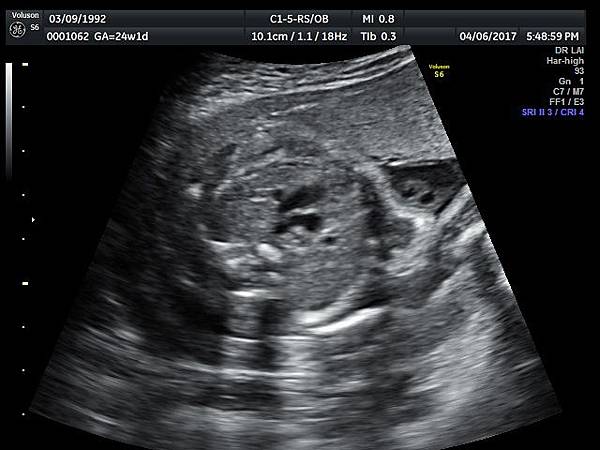

2017年4月6日25歲第一胎自然懷孕24週1天的孕婦,在我的診所接受胎兒心臟及高層次超音波檢查,檢查結果是持續性左側上腔靜脈(PLSVC)(附圖 4~6)合併輕微三尖瓣逆流,她的四指標篩檢唐氏症和愛德華氏症都是低風險,我的建議是抽羊水做傳統染色體及基因晶片檢查,如果擔心羊穿風險,可退而求其次做NIPS檢查。

- 4月 06 週四 201722:01

47 24 weeks isolated PLSVC